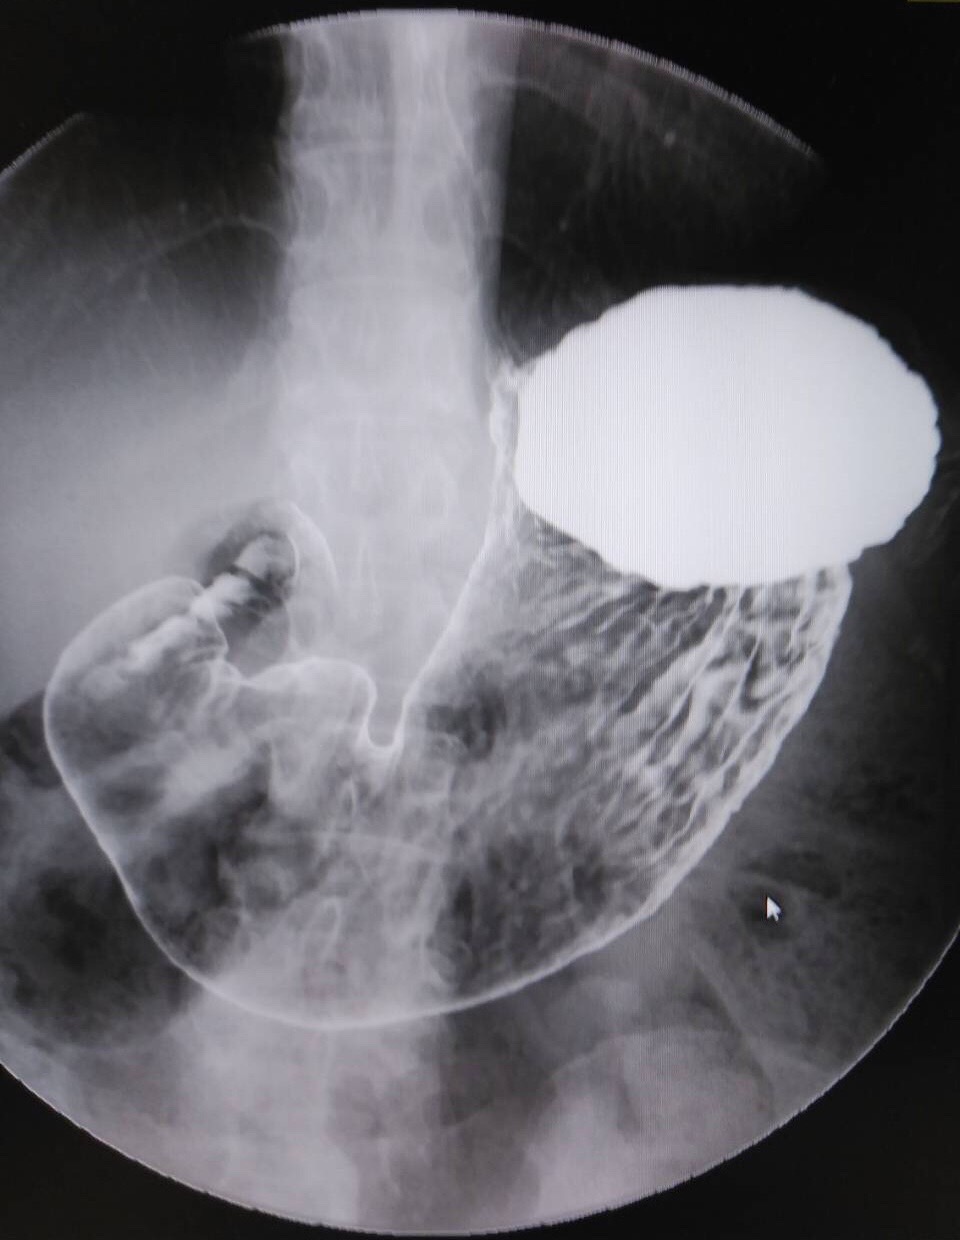

胃透視(胃バリウム)健診のおすすめ

勤続27年11ヶ月 診療放射線技師の松尾光弘です。 皆さんは自分自身の胃の形、胃の大きさはご存知ですか? 胃の形や大きさは内視鏡(胃カメラ)検査ではわかりません。 胃透視(胃バリウム)検査はそれがわかります。 胃の形には… 胃透視(胃バリウム)健診のおすすめ